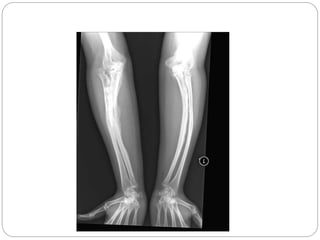

XRAY

 Generalized osteopenia

 Thinning of long bones

 #s in various stages of healing

 Vertebral compression & spinal #

 Skull enlarged, presence of wormian bone

XRAY  Generalized osteopenia Thinning of long bones  #s in various stages of healing  Vertebral compression & spinal #  Skull enlarged, presence of wormian bone